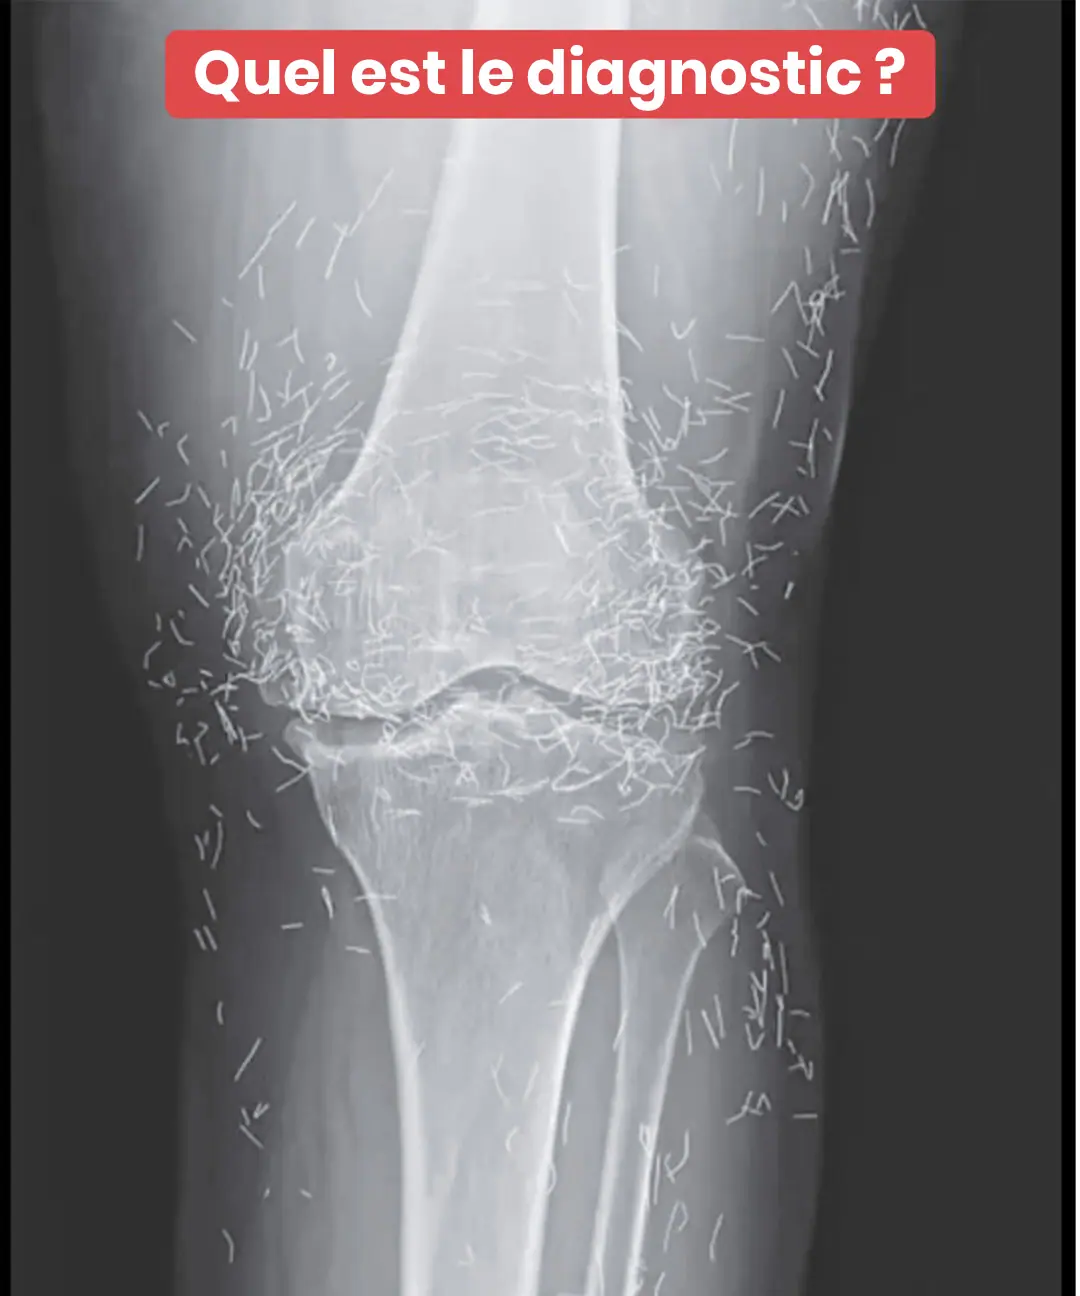

Imaginez passer une simple radiographie pour des douleurs aux genoux… et découvrir que votre corps renferme un véritable trésor caché ! C’est ce qui est arrivé à une femme de 65 ans, dont les clichés médicaux ont révélé une présence pour le moins inattendue. Ce que les médecins ont vu a soulevé bien plus de questions qu’il n’a apporté de réponses. Et derrière cette image intrigante se cache une pratique encore relativement méconnue en France, pourtant largement utilisée à travers le monde…

Comme beaucoup de femmes actives ou à la retraite, cette patiente originaire de Corée du Sud souffrait d’arthrose aux genoux. Cette affection, fréquente avec l’âge, provoque des douleurs persistantes, une raideur quotidienne et peut sérieusement limiter les activités du quotidien. Malgré plusieurs traitements conventionnels — antalgiques, anti-inflammatoires — ses douleurs persistaient, avec en prime des effets secondaires digestifs désagréables.

À ce stade, elle s’est tournée vers une alternative bien connue en Asie : l’acupuncture. Mais pas n’importe laquelle…